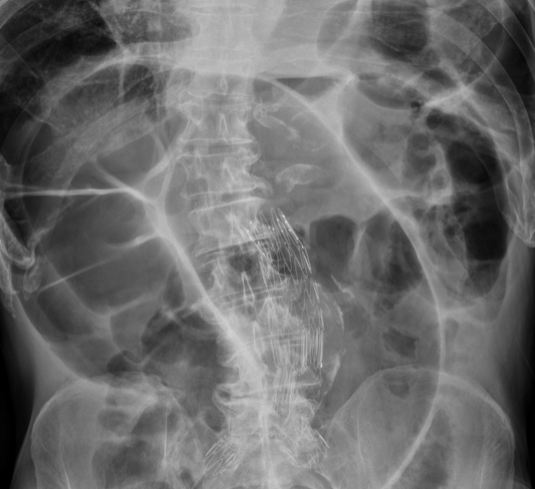

What is being shown on this abdominal x-ray?

What is this abdominal x-ray showing?

Cannot see psoas so AAA